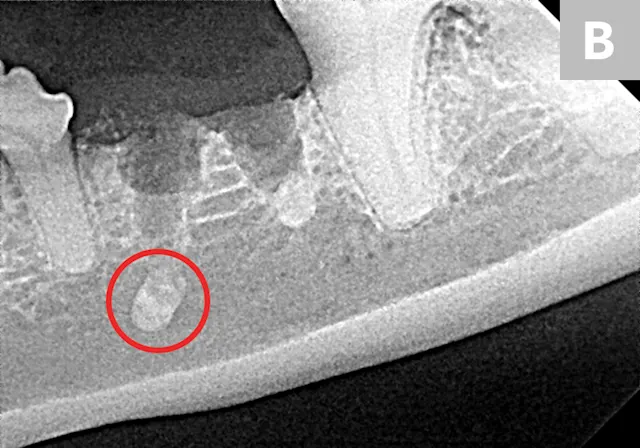

FIGURE 2

Right maxillary premolar tooth root in the nasal cavity (A; circle) and root fragment after removal from the nasal cavity (B)

Root removal from the nasal cavity can be especially difficult because of the large size of the nasal cavity and the potential for tooth root migration. Large mucoperiosteal flaps, bone windows, and suction can aid in the removal process. Avoiding the mandibular neurovascular structures when removing roots from the mandibular canal can be challenging but is crucial, as hemorrhage can occur if structures are punctured.